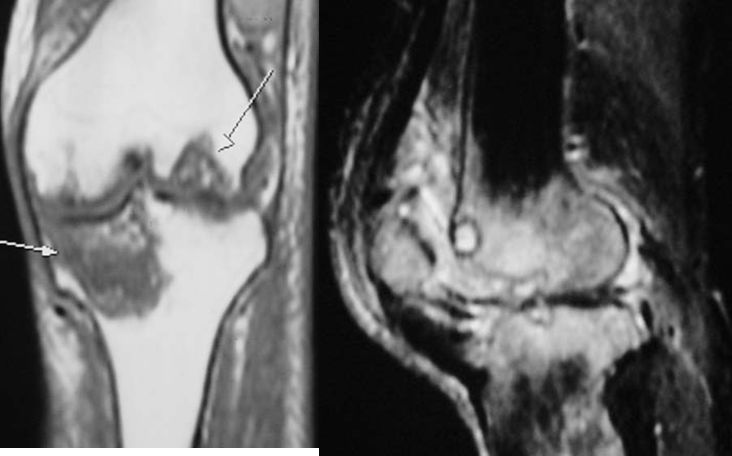

2、X线片(站立或负重位)示关节间隙变窄、软骨下骨硬化、和(或)囊性变、关节缘骨赘形成。

1、关节间隙变窄:成人膝关节间隙为4mm,小于3mm即为关节间隙狭窄,60岁以上的老人膝关节间隙为3mm,小于2mm为关节间隙狭窄。

2、软骨下骨板硬化:软骨下骨板致密、硬化,负重软骨下骨质内可见囊性改变。

3、骨赘形成。

软骨下骨板硬化